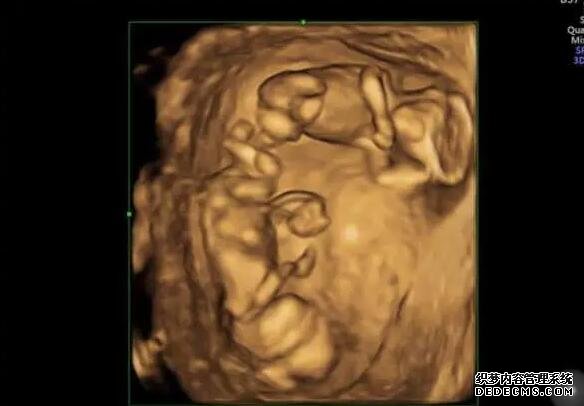

试管移植是一种辅助生殖技术,是许多不能自然怀孕的夫妻选择的方法。在试管移植过程中,女性需要注射人工促排卵药物来促进卵巢排卵。而在移植当天,打一针促黄体生成素能够帮助维持黄体功能,增加着床成功率,从而提高受孕率。